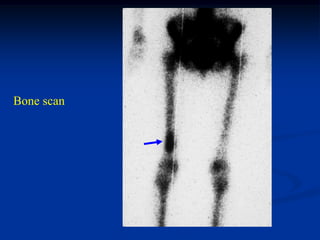

Case #549

48 year female

enchondroma femur

Bone scan